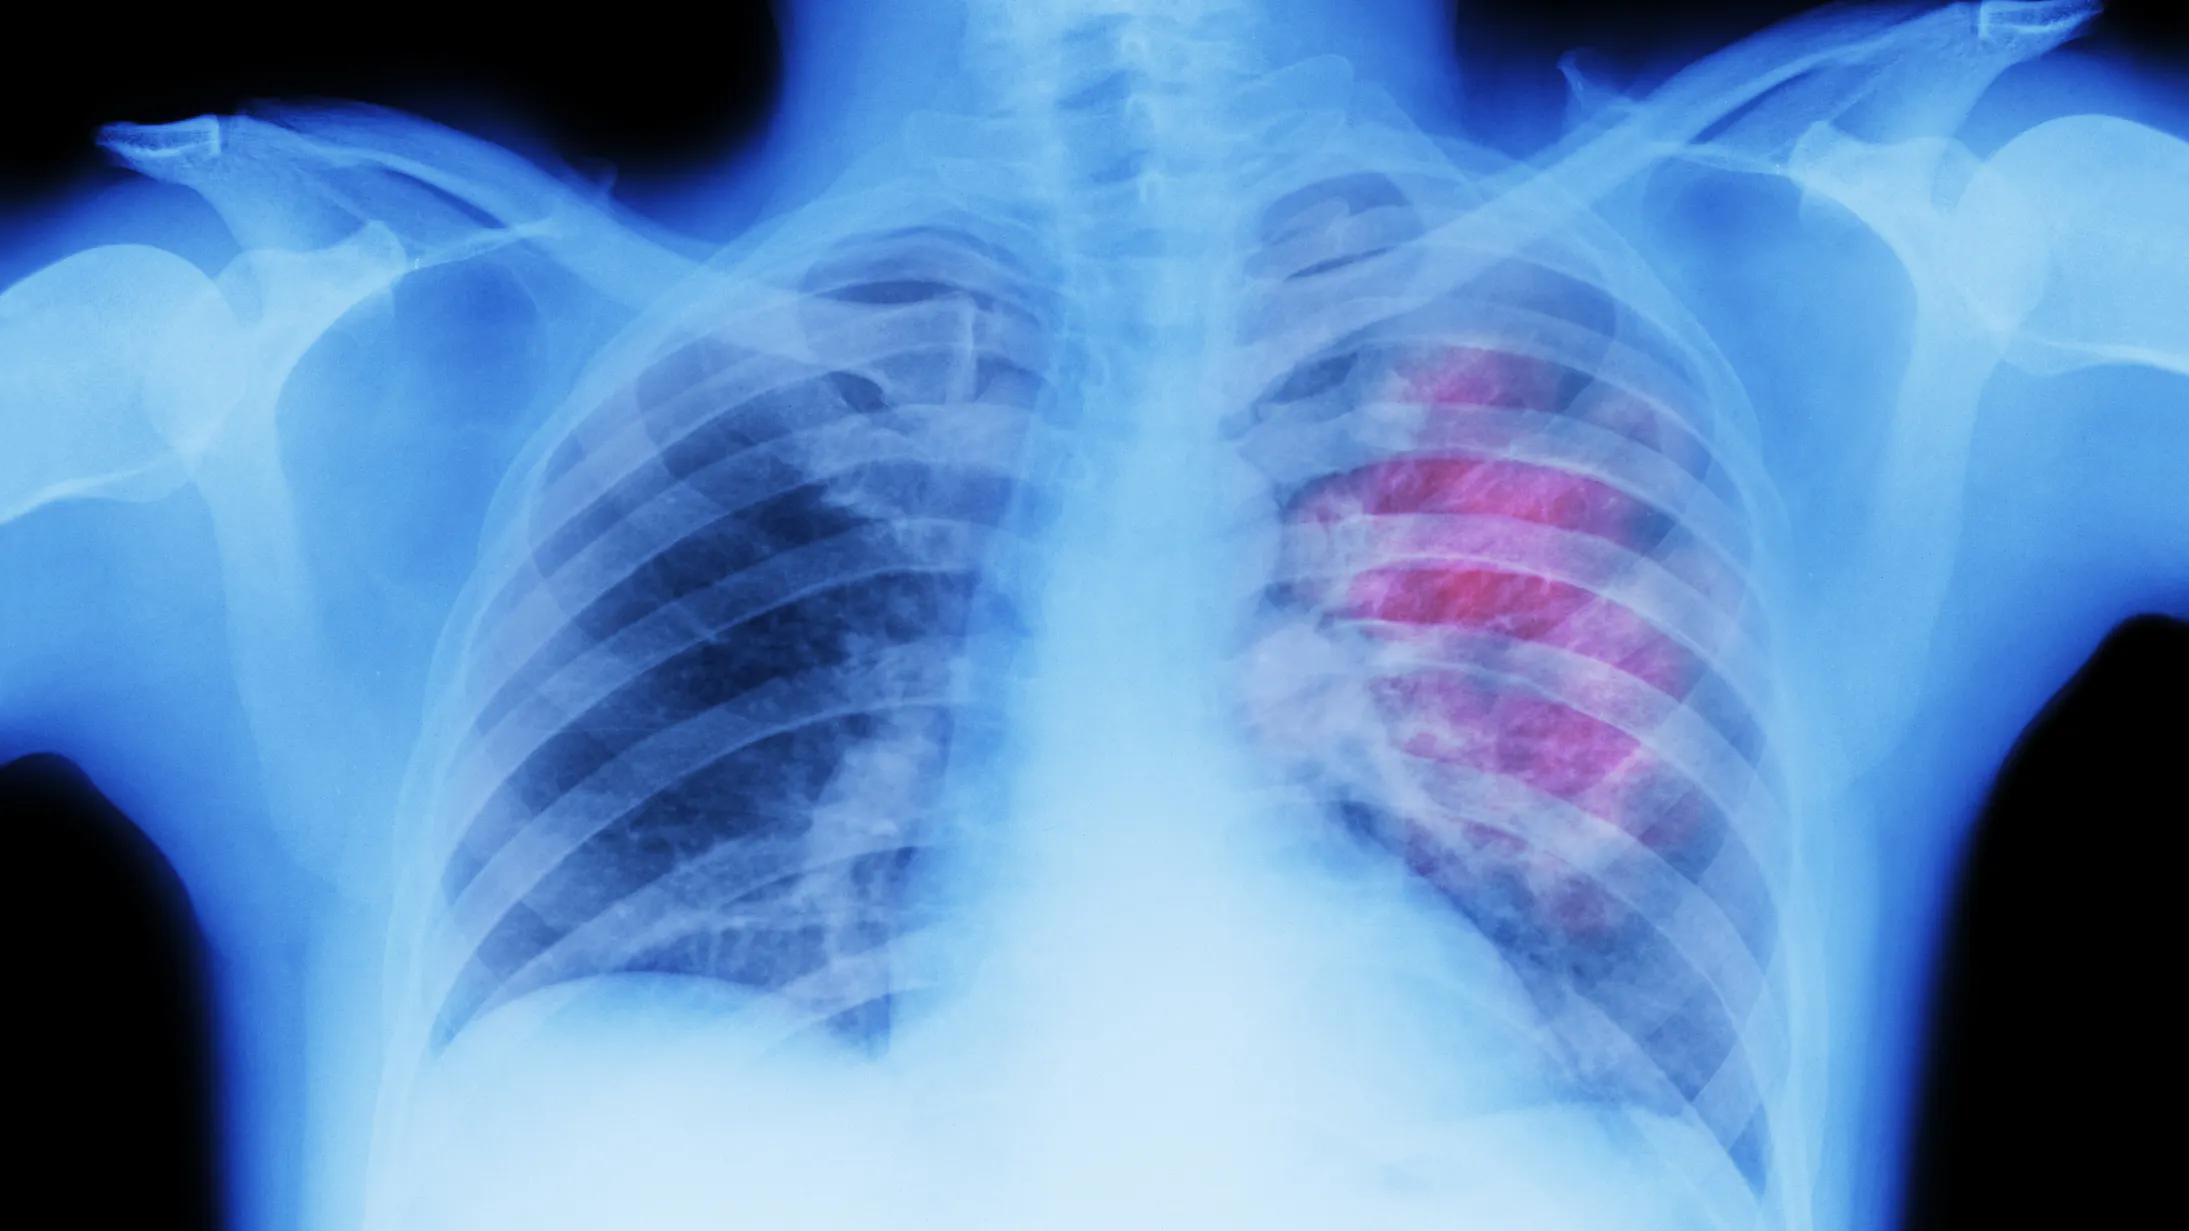

A new study indicates that an artificial intelligence tool can tremendously improve predictions of whether a nodule will develop cancer, thereby helping identify cancer much earlier in deadly diseases such as lung cancer.

Experts at the Royal Marsden NHS foundation trust, the Institute of Cancer Research, London, and Imperial College London created the new AI tool, which could identify nodules’ risk of cancer at significantly higher rates than current tests.

To ascertain how effectively the new tool performed, its accuracy was measured using a standard called area under the curve (AUC). A score of 1 would indicate a perfect record of predicting cancers; a 0.5 score would indicate a random guess. The new tool scored an AUC of 0.87, as opposed to the currently-used Brock score, which had an AUC of 0.67.